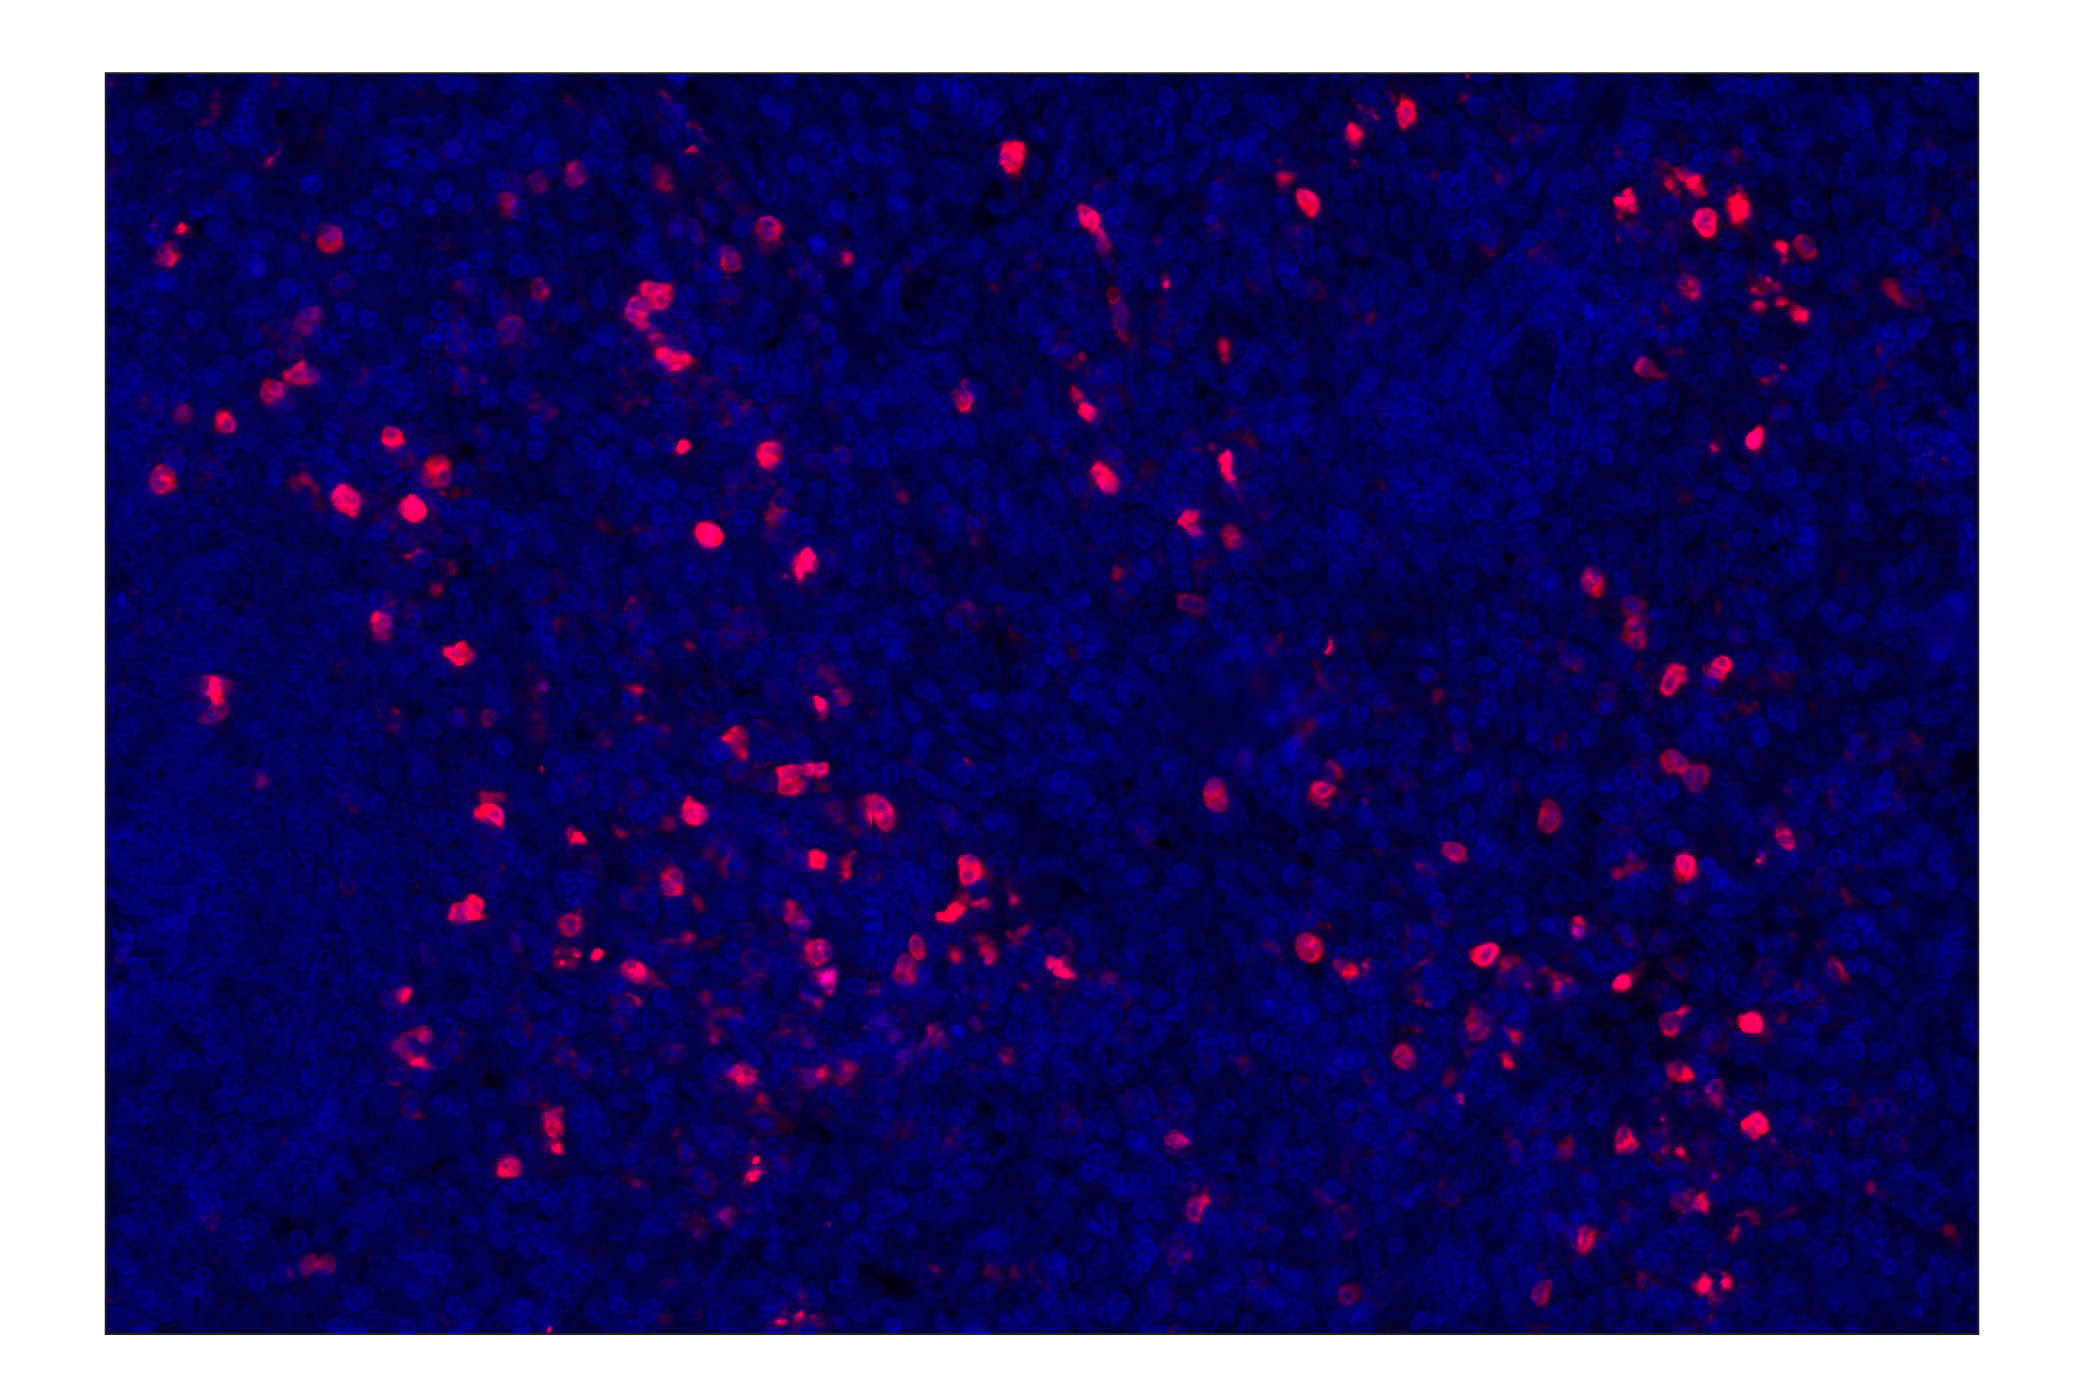

Eosinophil cationic protein (E6U5M) Rabbit Monoclonal Antibody (Alexa Fluor® 647 Conjugate) #15910

Immunohistochemistry (Paraffin) 1:100 - 1:400

Eosinophil cationic protein (E6U5M) Rabbit Monoclonal Antibody (Alexa Fluor® 647 Conjugate) recognizes endogenous levels of total Eosinophil cationic protein. This antibody does not cross-react with Eosinophil-derived neurotoxin protein.

Human